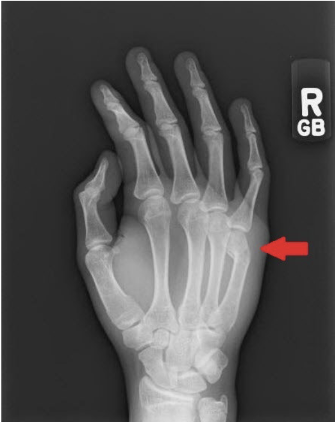

What is this fracture?

Boxer

What is boxer fracture?

Fracture of distal fifth metacarpal

Results from punching someone or something